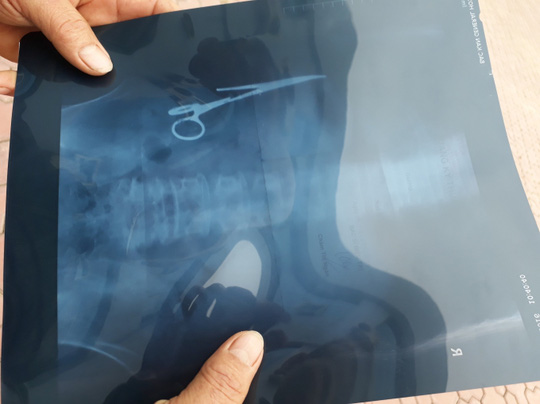

VBF-Những câu chuyện đùa về việc bác sĩ đãng trí và vô ý để quên đồ nghề khi mổ cho bệnh nhân tưởng chừng không có thực vậy mà tại VN đã xảy ra. Vụ việc có liên quan tới 1 bệnh nhân được mổ bụng sau tai nạn và cho tới nay là 18 năm vẫn luôn bị cơn đau hành hạ. Chỉ đến mới đây tình cơ đi siêu âm mới phát hiện ra chiếc kéo mà bác sĩ đã để quên.Bộ Y tế yêu cầu khẩn trương xác minh sự việc quên kéo dài 15 cm trong bụng một bệnh nhân 54 tuổi ở tỉnh Bắc Kạn trong suốt 18 năm, công khai thông tin và kết quả xác minh, xử lý.Ngày 29-12, Bộ Y tế đã yêu cầu Sở Y tế tỉnh Bắc Kạn xác minh thông tin về trường hợp của ông Ma Văn Nhật (54 tuổi, ở xã Bình Trung, huyện Chợ Đồn, tỉnh Bắc Kạn) bất ngờ được bác sĩ thông báo trong ổ bụng ông có một chiếc kéo dài.

Bộ Y tế yêu cầu công khai thông tin và kết quả xác minh, xử lý cho cơ quan truyền thông, báo cáo về Cục Quản lý Khám, chữa bệnh (Bộ Y tế) trước ngày 6-1-2017.Trước đó, thấy đau nhói ở bụng sau một lần làm việc quá sức, ông Ma Văn Nhật (54 tuổi, ở xã Bình Trung, huyện Chợ Đồn, tỉnh Bắc Kạn) vào Bệnh viện Gang thép Thái Nguyên khám. Kết quả siêu âm ngày 25-12 cho thấy trong ổ bụng của ông có một chiếc kéo dài khoảng 15 cm, được cho là chiếc panh chuyên dùng để mổ của ngành y. 2 ngày sau, ông đến siêu âm tại Bệnh viện đa khoa Bắc Kạn cũng cho kết quả tương tự.

Theo ông Nhật, ngoại trừ lần phẫu thuật cách đây 18 năm, ông chưa bao giờ phải vào viện mổ lần nào. Thời điểm đó vào tháng 6-1998, ông bị tai nạn giao thông khiến ghi đông xe đâm vào mạng sườn. Ông được chuyển từ bệnh viện huyện ra Bệnh viện Đa khoa tỉnh Bắc Kạn và được chỉ định phẫu thuật. Sau ca phẫu thuật, ông vẫn ăn uống và sinh hoạt bình thường. Ông Nhật cho biết thi thoảng ông cũng thấy đau nhưng lúc đó vẫn còn chịu được, với lại cứ 1-2 ngày là hết đau nên ông cố chịu, cộng thêm nhà trong rừng, không tiện đi bệnh viện nên từ đó đến nay ông chưa đi viện kiểm tra lần nào. Hiện giấy ra viện, giấy chứng nhận phẫu thuật ông đã nộp cho bên công an để làm hồ sơ.Một lãnh đạo Bệnh viện Đa khoa tỉnh Bắc Kạn cho biết đã nhận được phản ánh của ông Nhật và đang cho kiểm tra lại xem những nhân viên y tế nào tham gia kíp mổ cho bệnh nhân năm 1998. Khi đó, bệnh viện sẽ họp và đưa ra hướng xử lý cụ thể. Tuy nhiên, thời gian đã lâu, hồ sơ bệnh án đã bị hủy. Trong khi đó, lãnh đạo Sở Y tế Bắc Kạn cho biết Sở đã chỉ đạo bệnh viện làm việc với gia đình người bệnh để đưa ra phương án tốt nhất. Quan trọng là phẫu thuật lấy dị vật ra, sẽ mời các chuyên gia của Bệnh viện Việt Đức tham gia ca mổ để đảm bảo an toàn nhất cho người bệnh.